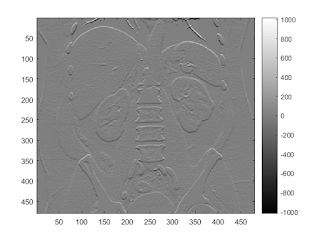

sobel edge filter

b = fspecial('sobel'); I2 = conv2(I,b,'same'); imagesc(I2); colorbar